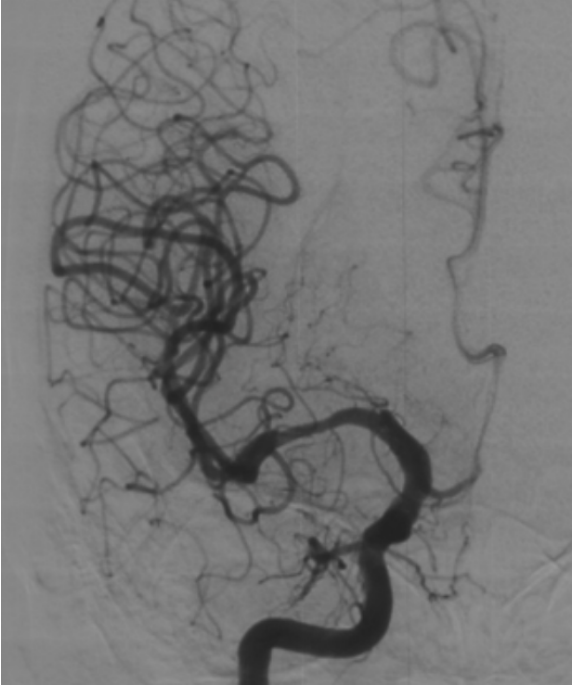

血管造影显示右侧MCA重度狭窄,近端血管直径3mm,紧邻狭窄远端 2.8mm,远端近分叉部直径3.8mm

在放大的血管造影上看,可见外侧豆纹动脉在远端紧邻狭窄部位发出

由于担心球囊扩张后的雪犁效应,影响豆纹动脉的通畅性,选择比较保守的gateway球囊 2.75*15进行扩张

DSA复查(2019-10-31)提示严重支架内狭窄,豆纹动脉及早期颞支动脉依然保持通畅